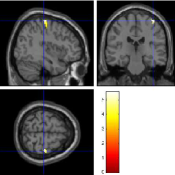

Once the reduced FOV images are available, the proposed pMRI 4D-UWR-SENSE algorithm and its early UWR-SENSE version have been utilized in a final step to reconstruct the full FOV EPI images and compared to the mSENSE Siemens solution. For the wavelet-based regularization, dyadic Symmlet orthonormal wavelet bases [48] associated with filters of length 8 have been used over resolution levels. The reconstructed EPI images then enter in our fMRI study in order to measure the impact of the reconstruction method choice on brain activity detection. Note also that the proposed reconstruction algorithm requires the estimation of the coil sensitivity maps (matrix in Eq. (2)). As proposed in [4], the latter were estimated by dividing the coil-specific images by the module of the Sum Of Squares (SOS) images, which are computed from the specific acquisition of the -space centre (24 lines) before the scans. The same sensitivity map estimation is then used for all the compared methods. Fig. 5 compares the two pMRI reconstruction algorithms to illustrate on axial, coronal and sagittal EPI slices how the mSENSE reconstruction artifacts have been removed using the 4D-UWR-SENSE approach. Reconstructed mSENSE images actually present large artifacts located both at the centre and boundaries of the brain in sensory and cognitive regions (temporal lobes, frontal and motor cortices, …). This results in SNR loss and thus may have a dramatic impact for activation detection in these brain regions. Note that these conclusions are reproducible across subjects although the artifacts may appear on different slices (see red circles in Fig. 5). One can also notice that some residual artifacts still exist in the reconstructed images with our pipeline especially for . Such strong artifacts are only attenuated and not fully removed because of the high level of information loss at .

| mSENSE | 4D-UWR-SENSE | ||

| Axial |  |

|

|

| Coronal | |||

| Sagittal | |||

| Axial |  |

|

|

| Coronal | |||

| Sagittal |